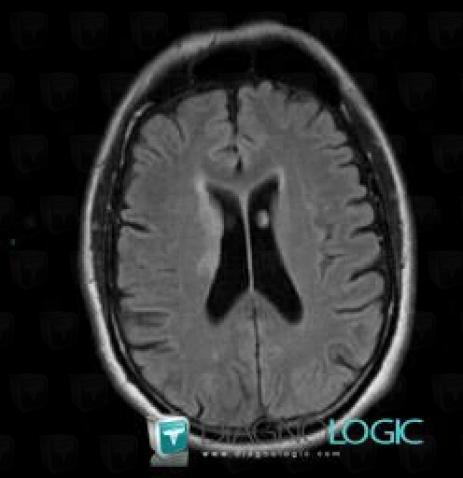

Cerebral infarction, Basal ganglia and capsule, MRI

Here is the specific information in the key image above:

- Diagnosis Cerebral infarction, Location(s) Basal ganglia and capsule, with gamuts Basal ganglia T2W or FLAIR hyperintense lesion